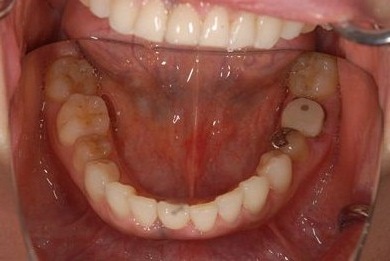

治療前

• 治療前